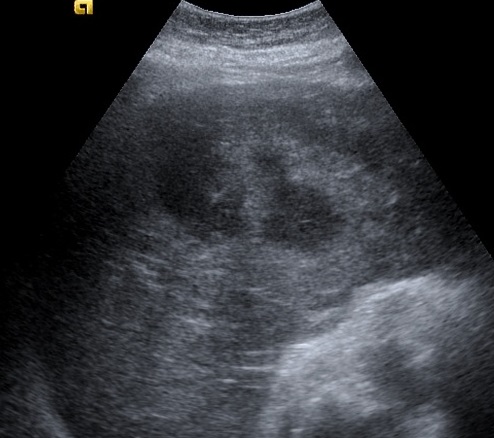

Áspect echographique d'une

abces du foie : C'est une masse ovalaire hypoechogen

en cloisone et a paroie hyperechogen

.Sans renfocement ou renforcement legere de

ascoustique posterieure |